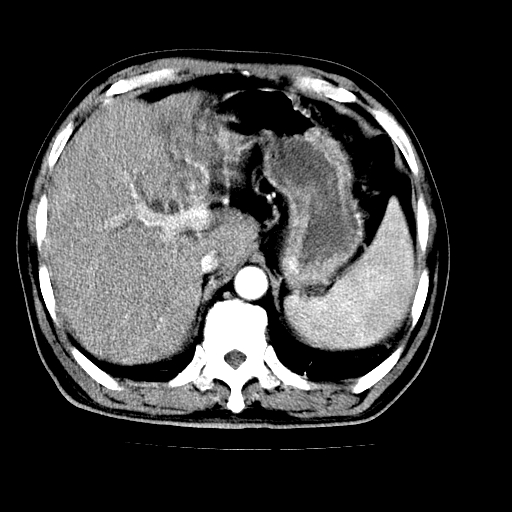

男,66岁,上腹部不适、黄染一周。彩超示:肝左叶占位,肝内胆管扩张,胆总管扩张,胆总管占位?

肝左叶不规则软组织肿块影,边缘不规整邻近肝实质受累分界不清;肝内胆管(左叶)明显扩张成“软藤状”,诊断:肝左叶胆管细胞癌。

肝左叶占位性病变,并胆管扩张,符合胆管细胞癌ct表现,门脉左支受累,左肾囊肿。窗宽太窄了,其他的看不清

肝左叶不规则软组织肿块影,边缘不规整邻近肝实质受累分界不清;肝内胆管(左叶)明显扩张成“软藤状”,诊断:肝左叶胆管细胞癌。胆囊钙乳症。

支持 1肝左叶肝内胆管细胞癌伴胆总管及门脉左支受侵。2胆囊钙乳症。

支持 1)肝左叶胆管细胞癌伴胆总管及门脉左支受侵。2)胆囊钙乳症。